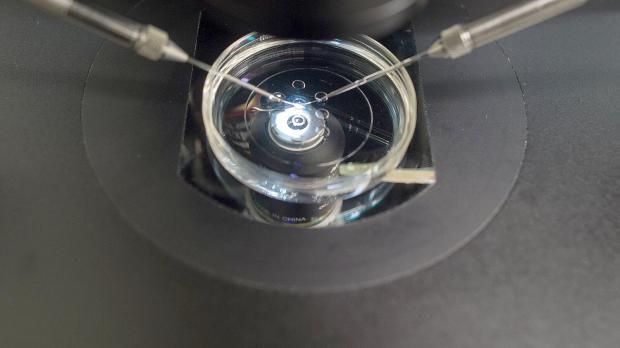

Eine seltene Mutation im Sperma eines dänischen Spenders erhöht das Krebsrisiko erheblich. Reporter decken auf: Der Mann ist biologischer Vater von mindestens 197 Kindern in verschiedenen Ländern.

Das Sperma eines dänischen Samenspenders, bei dem eine gefährliche genetische Mutation festgestellt wurde, soll Berichten zufolge zur Zeugung von knapp 200 Kindern in Europa genutzt worden sein.

Den Recherchen zufolge, an denen unter anderem Reporter der Deutschen Welle und des ORF beteiligt waren, erhöht der Gendefekt im Sperma des anonymen Spenders das Risiko von Krebserkrankungen erheblich. Es wurde demnach in 20 Prozent seiner Spermien nachgewiesen. Mindestens 197 Kinder sollen mit den Samen des Mannes gezeugt worden sein. Wie viele davon von dem Gendefekt betroffen sind, ist nicht bekannt.

Es handle sich um eine zuvor unbekannte Mutation, die nur in einem kleinen Teil der Spermien auftrete, so die Mitteilung weiter. Der Spender selbst und seine Familie seien nicht erkrankt und eine Mutation dieser Art könne durch genetisches Screening vorsorglich nicht erkannt werden. Als der Gendefekt bestätigt worden sei, habe man den Spender unverzüglich gesperrt und Behörden und Kliniken informiert. Verantwortlich für die Informierung der Betroffenen seien aber die Kliniken.